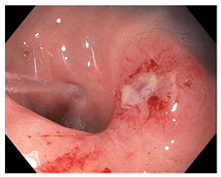

| Endoscopy | Flat white scar Telangiectasia Absence of ulcers and mucosal nodularity | Small mucosal nodules/minor mucosal irregularities Superficial ulceration Mild, persistent erythema of the scar | Visible tumor |

| Superficial ulceration | ![]() | ![]() | ![]() |